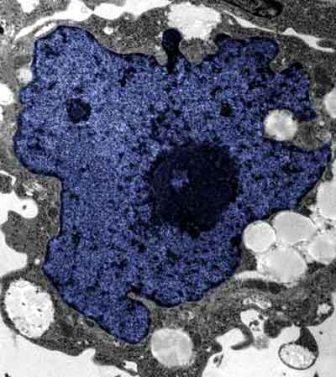

在成人體內及胚胎內發(fā)現(xiàn)的干細胞屬于主細胞,能發(fā)育成各種各樣的組織,可作為人體“修補工具箱”,取代死去及腐壞細胞組織。此前,最可行的干細胞為胚胎干細胞,但它的使用一直受到爭議,因為要在胚胎抽取干細胞會令胚胎死亡,有人認為這樣是變相奪走一條生命。

2007年,日本京都大學教授山中伸彌為首的科研小組證明,利用病毒倒撥普通皮膚細胞的“生理時鐘”,可把它們變成像胚胎干細胞那樣具備“變身”能力的細胞。但利用病毒把基因輸入細胞,有可能導致癌癥。這即是說使用這些細胞的風險很大。

來自英國和加拿大的兩組研究員所用的新方法不必使用病毒。這項新突破暗示科學家現(xiàn)在能更認真地看待在醫(yī)學中利用皮膚干細胞(即誘導多功能干細胞,俗稱“iPs”細胞)的前景。

這些細胞只要配以適當?shù)幕瘜W品和蛋白質,就能轉化成腦神經(jīng)元、制造胰島素的胰腺細胞、骨或軟骨、心臟肌肉,或其它多種組織。這些細胞利用病人皮膚來培育,更暗示它們不會被人體排斥。